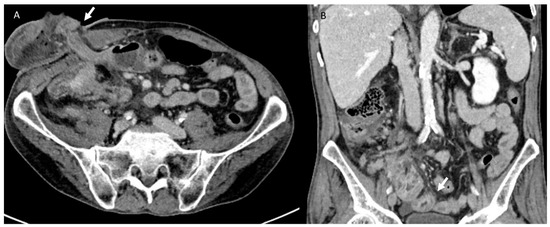

3.3. Bleeding